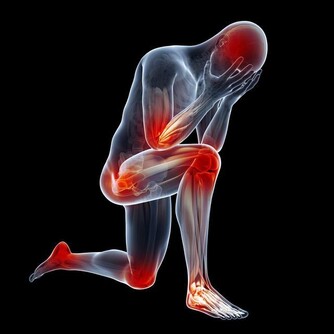

7. 你的肌肉感覺不太好,並容易痙攣

當你喝太多水時,電解質水平下降,身體平衡受到影響。而低電解質水平會導致一些令人不快的症狀,包括肌肉痙攣和痙攣。